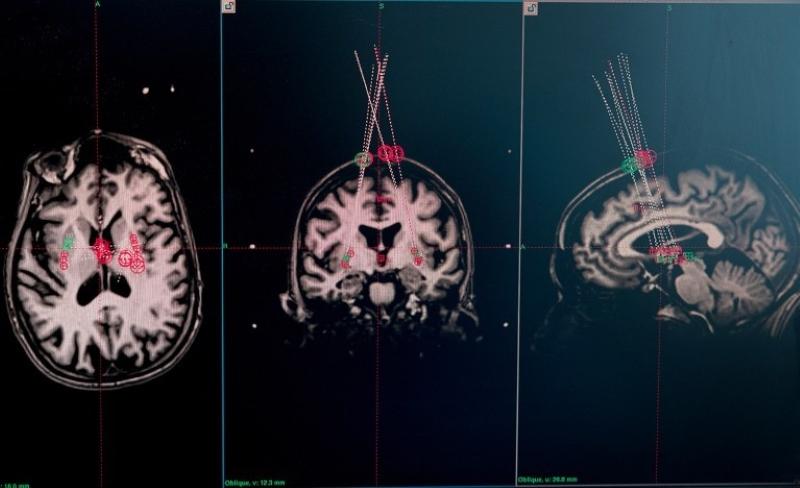

关于癫痫的研究同样值得关注。在美国神经元治疗公司开展的临床试验中,外科医生借助干细胞疗法,将干细胞整合到15名癫痫患者的神经回路中。移植一年后,其中两名参与者严重癫痫发作的频率几乎降至零,且效果已经持续了两年。其他大多数参与者的癫痫发作频率也显著降低。该公司报告称,这一疗法没有明显副作用,也没有造成认知损伤。基于上述效果,包括神经元治疗公司在内的团队打造的“有效干细胞疗法”,也被《麻省理工技术评论》评为2025年“十大突破性技术”之一。